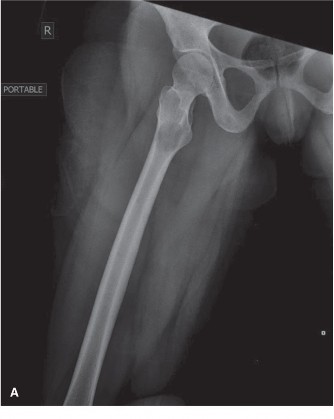

A 56-year-old male is referred to your office by his primary physician, with concern for metastatic disease. …